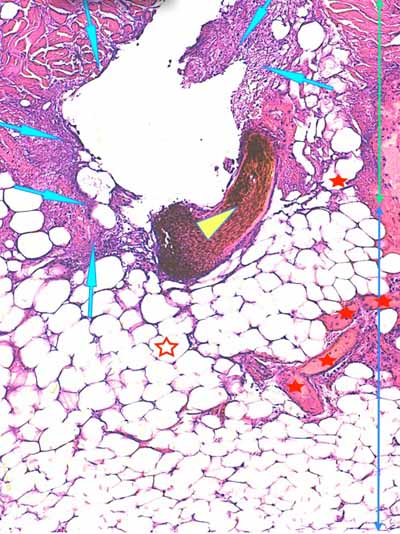

Photo 7 (Hémalun-Eosine X40) : l’hypoderme et le muscle peaucier sont dilacérés

par l’œdème et un infiltrat cellulaire diffus. Un vaisseau sanguin de moyen calibre contient un thrombus fibrineux.

Légendes de la Photo 7 :

- Flèches turquoises : muscle peaucier

- Flèches juanes : œdème et infiltrat neutrophilique dilacérant l’hypoderme et le muscle peaucier

- Ovale turquoise : la lumière d’une veine de moyen calibre est obstruée d’un thrombus fibrineux

- Double flèche verte : épaisseur dermique

- Double flèche bleue : épaisseur hypodermique

- Étoiles bleues : follicules pileux

Photo 9 (Hémalun-Eosine X200) : une artériole hypodermique de moyen calibre

montre une vacuolisation de ses cellules endothéliales et un épaississement

de sa media et de son adventive. Sa lumière abrite un fragment de

thrombus fibrineux. L’hypoderme environnant est œdémateux.

Légendes de la Photo 9 :

- Flèches jaunes : vésiculation de l’espace sous-endothélilae et des cellules endothéliales

- Flèches turquoises : œdème et infiltrat neutrophilique dilacérant les adipocytes des lobules adipeux de l’hypoderme

- Pointe de flèche turquoise : adipocyte

- Ovale rouge pointillé : artériole de moyen calibre

- Ronds verts : endothélium de l’artériole

- Ronds noirs : media de l’artériole

- Ronds bleus : adventice de l’artériole

- Double flèche bleue : hypoderme

- Étoile rouge : thrombus fibrineux ostruant la lumière de l’artériole